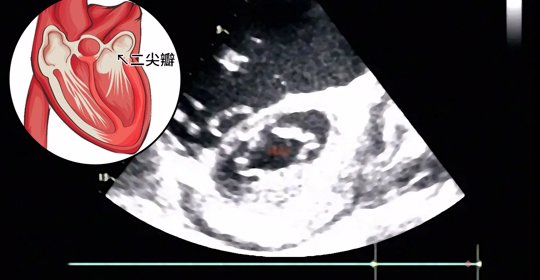

心肌病變是指心臟肌肉組織的結構或功能的異常變化,這種變化可能影響心臟的正常收縮和泵血功能。其中最常見的擴張型心肌病是因為心室擴大,失去了正常的收縮力,由於心肌細胞的死亡或損傷,使心臟無法有效地泵血,擴張型心肌病變的病因是多因素的,包括遺傳和環境因素。

擴張型心肌病變又稱為充血性心臟病、肥厚型心肌病,主要影響心臟的肌肉組織,使心臟變得擴張且失去正常的收縮力。 由於左心室擴大,心肌厚度呈正常或變薄,心肌收縮變得較無力,造成左心室在收縮時,沒有辦法將足夠血液泵送出心臟,從而引起心臟衰竭。